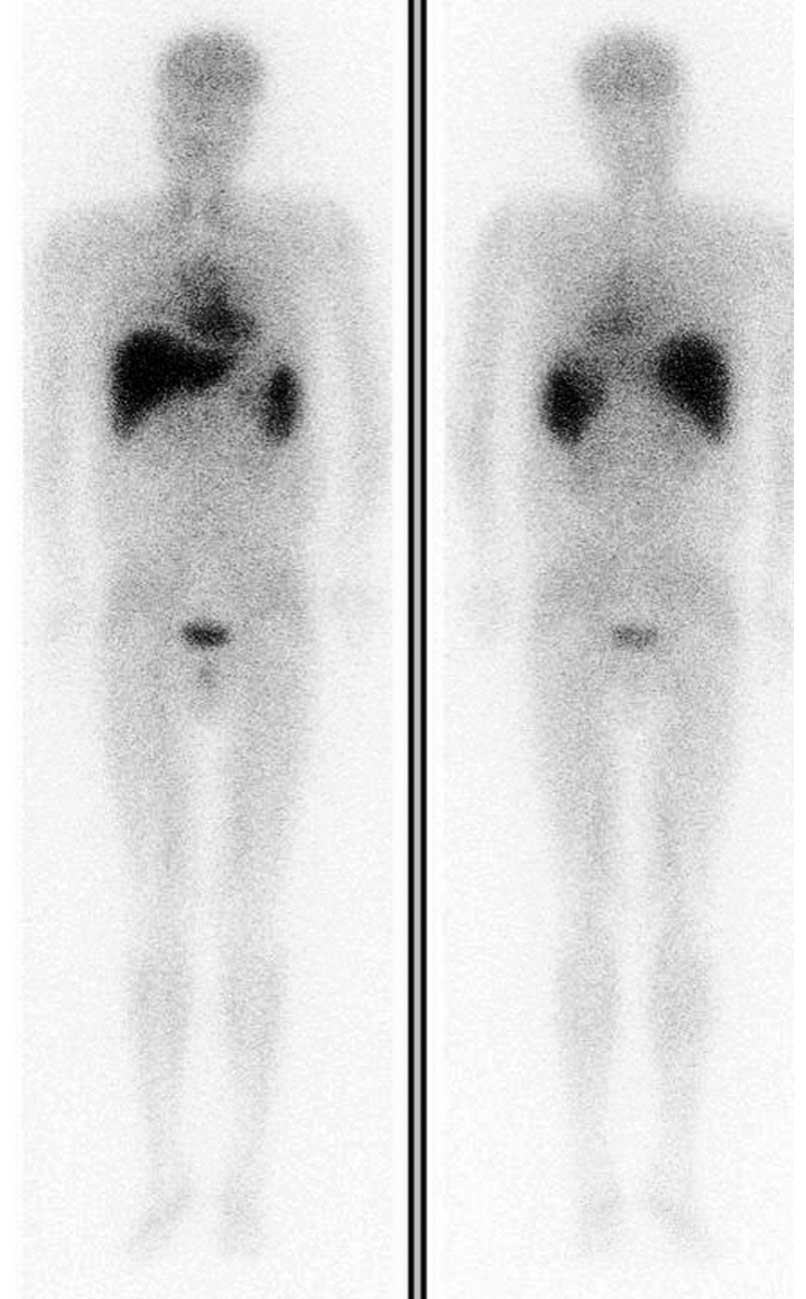

Safety and efficacy of a peripheral intravenous bolus of Licartin for the treatment of advanced hepatocellular carcinoma

The aim of the present study was to examine the safety and efficacy of a peripheral intravenous bolus of Licartin for the treatment of advanced hepatocellular carcinoma (HCC), and to explore the clinical value of this treatment. Clinical data from Tianjin Medical University Cancer Institute and Hospital (Tianjin, China) were analyzed. Thirty‑three patients (38 cases) with advanced HCC received an intravenous bolus of Licartin. The patients underwent routine blood examinations and liver, kidney and thyroid function tests 1 week prior to treatment and 1 and 3 months after treatment, and a long-term follow‑up was performed. These data were collected before and after treatment was statistically analyzed and compared with that of previous studies regarding the safety of Licartin combined with transcatheter arterial chemoembolization for the treatment of HCC. During treatment, adverse reactions, including non‑infectious fever, pain in the liver area, nausea and vomiting, occurred in a minority of patients. The adverse reactions were endured in the majority of cases and the symptoms were spontaneously relieved. Following treatment, 15 patients (39.47% of cases) demonstrated drug‑related adverse reactions, including decreased white blood cell counts, platelet counts, hemoglobin levels and neutrophil counts, and increased levels of alanine aminotransferase, aspartate aminotransferase, serum direct bilirubin, creatinine and blood urea nitrogen, from high to low incidence. Electrocardiograms indicated no significant differences in thyroid function between patients before and after treatment, and showed stable vital signs. This study demonstrated that peripheral intravenous bolus administration of Licartin for radioimmunotherapy is safe and effective, is tolerated by the patient and may potentially become a routine treatment for HCC.

Figure 1

Figure 2